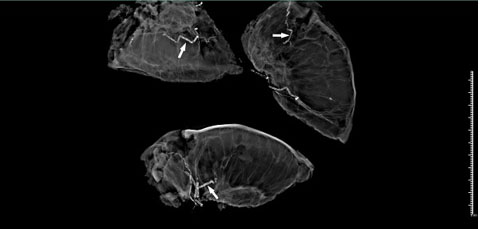

Excised tissue was evaluated using FaxitronTM high-resolution radiographic imaging, which revealed extensive vascular calcifications, particularly within the subcutaneous arterioles (Figure 3). These findings prompted targeted histopathologic analysis, which demonstrated medial calcification, intimal hyperplasia, and luminal occlusion, confirming the diagnosis of calciphylaxis (Figure 4). Notably, these diagnostic features were not present in the initial punch biopsy, highlighting the limitation of conventional biopsy techniques and the added value of FaxitronTM imaging in guiding targeted tissue examination.

Figure 3: FaxitronTM digital radiographic image of excised tissue. The image demonstrates prominent calcifications within the vessels (arrows), guiding targeted histopathological analysis.